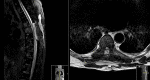

Brown-Séquard syndrome (BSS) is a rare neurological condition caused by a hemi-lesion of the spinal cord and was first described in the 1800s. BSS is characterized by an ipsilateral absence of motor control and discriminatory/proprioceptive/vibratory sensation at and below the spinal level involved, associated with loss of contralateral temperature and pain sensation a couple of vertebral segments below the lesion. BSS is commonly associated with trauma, but can also be iatrogenic. The authors report a case of a patient who presented with neoplastic dorsal spinal cord compression and developed a BSS after surgical decompression and review of the literature of postoperative BSS cases.